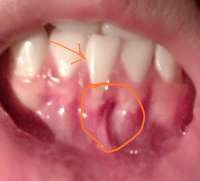

Вот такая херня уже в течение двух месяцев. Не проходит. Появилась она после поедание чипсов. Сначала была небольшого размера, теперь как на фото. Не болит, не зудит, жжения никакого.Что это?

>>920835Реактивная, то есть возникла как ответ на раздражение-частая травматизация, прикусывание этого места. Не опасно, самостоятельно не исчезнет, но может мешать и постоянно попадать между зубами.